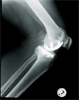

Post

Op

Post Operation photo